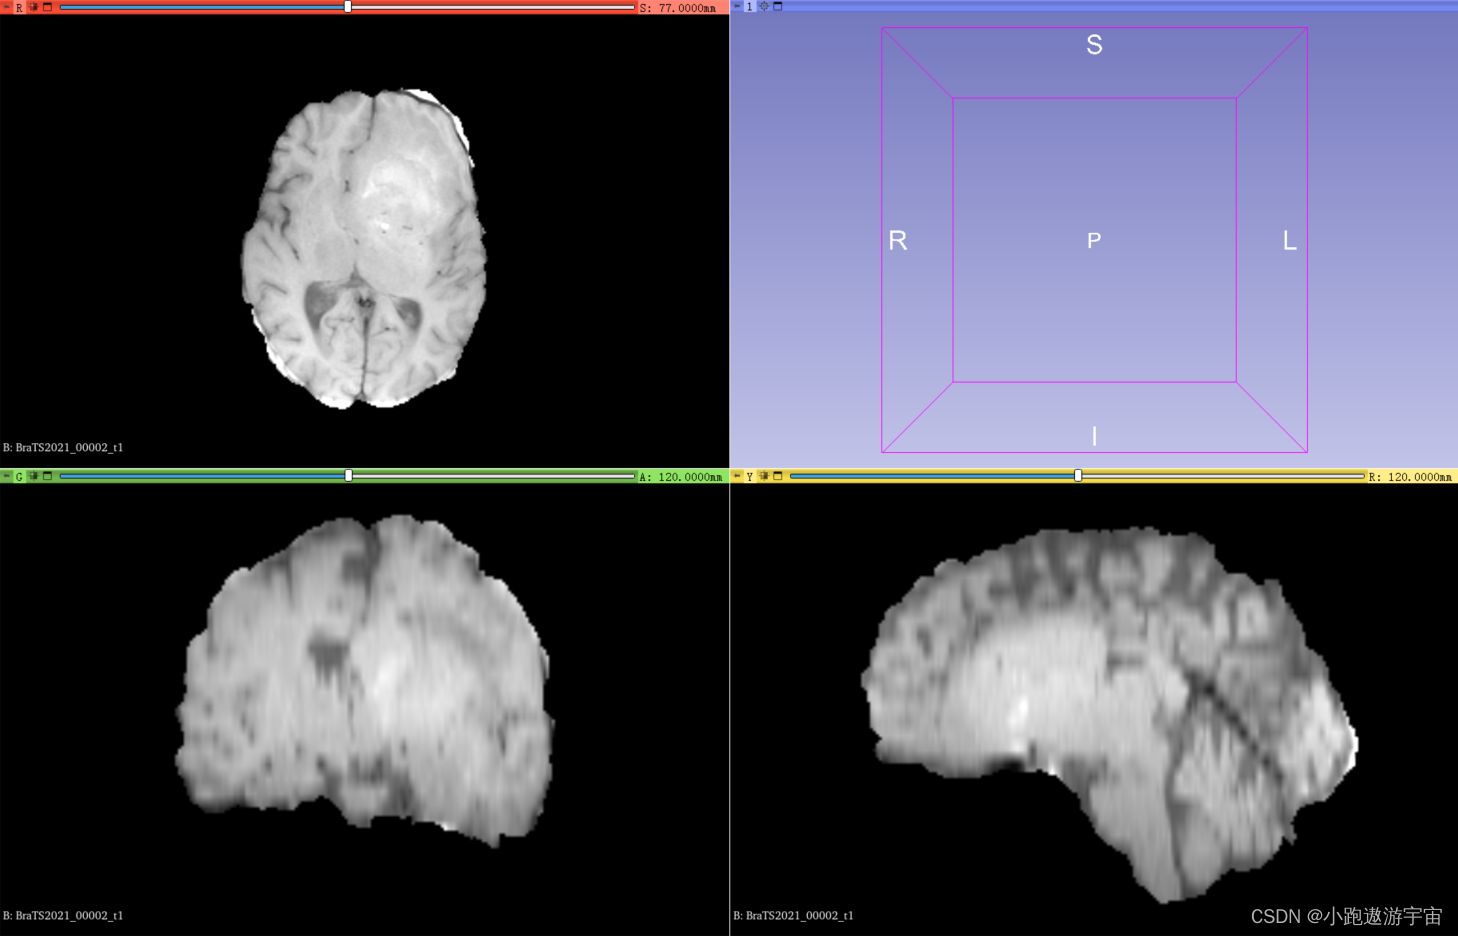

T1加权成像(T1-weighted imaging, T1):这种成像方式通过对人体进行磁共振成像,使用对T1信号敏感的成像方法,呈现出人体组织的强度。T1序列主要用于显示解剖结构。

BraTS2021_00002_t1.nii.gz